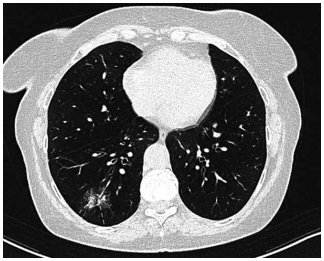

Mulher de 31 anos, recentemente diagnosticada com

leucemia mieloide aguda, é internada com neutropenia

febril doze dias após o primeiro ciclo de quimioterapia de

consolidação com citarabina em altas doses. Ela é tratada adequadamente com cefepima intravenosa. Sete

dias após, as hemoculturas são negativas e a contagem

de leucócitos está começando a se recuperar. Ela agora

apresenta febre de 38 °C, tosse e desconforto torácico

pleurítico. Os níveis séricos de galactomanana e beta-glucana estão elevados. A tomografia de tórax realizada

agora é mostrada a seguir: